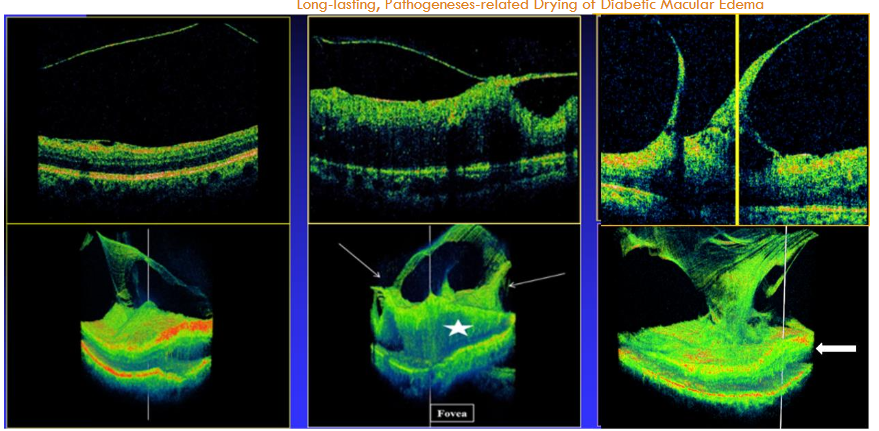

Most existing OCT scans utilize 2D image slices, thereby missing the complex 3D structure of the VRI. When OCT B-scans cross the fovea, they may detect two of the DDME pathogeneses: vitreofoveal traction (VFT) and epimacular membrane (ERM). OCT scans often employ raster or radial lines, which leave the significant areas between scanned lines unexamined, as previously discussed. By comparison, continuous scanning systems, such as the 3D spectral-domain OCT (SD-OCT) 1000 (Topcon, Japan), provide more precise imaging of the VRI by scanning every point in the examined area. These continuous scans also provide the ability to view the examined field in 3D images and video clips (which differ from a 3D block). These 3D images thus exposed the overlooked vitreoretinal extrafoveal traction (ExFT) membranes and their traction sites, as well as their association with the centrally-involved DDME (Figure 1). ExFT site may appear in any spot in the area centralis, as explained.

The 3D diagnostic information is essential since the meridian of the posterior vitreous cortex (PVC; posterior hyaloid =PH) at the ExFT site is regularly different from that of the macula. The rest of the PH is anteriorly detached and appears in the different B-scan meridians as several free-floating membranes, as previously explained. Vitreopapillary traction (VPT) is a relatively common type of ExFT, detectable by B-scans (Figure 1). ExFT is often linked to splitting of the PVC into anterior and posterior lamellae, i.e., vitreoschisis.

A study (n= 58 eyes/ patients) using the 3D SD-OCT 1000 identified the following prevalence of DDME pathogeneses: VFT in 19%, ERM in 22.4%, ExFT (including VPT) in 34.5% (making ExFT the most common pathogenesis), and transitional-phase (previously termed ‘vasogenic’) DDME, after excluding ExFT, accounted for 24.1%. Other studies have verified the association between ExFT and DDME. (Adie’s study termed ExFT “adhesions-pegs,” and reported a prevalence of 41%. Therefore, based on these data, in eyes treated with medications or laser following the exclusion of VFT and ERM, the mean expected ratio of ExFT to transitional-phase DDME is >34.5/24.1= ≥60/40%. Researchers have emphasized the importance of 3D-OCT imaging in evaluating the VRI in pathologies other than DME.

To achieve long-lasting macular drying following exclusion of MA-related DME and overt macular ischemia, early PPV and ILM peeling in naïve-treatment eyes may be considered the primary treatment, irrespective whether traction is detected or not. Systemic factors influencing DME should also be best controlled. However, in cases in which GLP is preferred, advanced OCT imaging is essential to exclude ExFT before proceeding. When appropriate 3D OCT is unavailable, or when widefield OCT images are indefinite, detecting free-floating PH segments by B-scans should guide a search for ExFT membrane(s). This, by rescanning the PH route in various areas, looking for its contact site in the area centralis. In case of detecting ExFT, rescanning between the edema underlying the traction site (Figure 1, central) and the foveal edema is essential to verify or exclude continuity of the ExFT-related edema and the central DDME. Other options for detecting ExFT sites were earlier described. When ExFT associated with the DDME is unequivocally excluded, GLP may be considered.